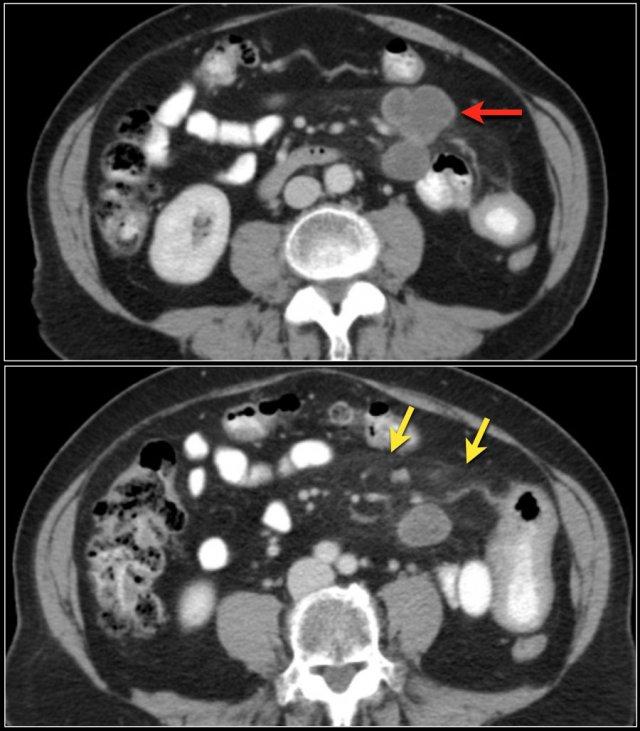

Khối nhỏ trong lòng hồi tràng (mũi tên vàng). U carcinoid ruột non kèm theo khối mạc treo dạng tua gai với phản ứng xơ hóa desmoplastic lân cận.

Đây là hình ảnh điển hình của u carcinoid biểu hiện là một khối mạc treo lớn với phản ứng xơ hóa desmoplastic và co kéo các quai ruột non lân cận kèm dày thành ruột (các mũi tên).

U carcinoid có vôi hóa và phản ứng xơ hóa desmoplastic. Tắc ruột non do thành phần trong lòng ruột của u carcinoid. Lưu ý tổn thương di căn gan nhỏ (mũi tên).

Các hình ảnh cho thấy u carcinoid biểu hiện là một khối tăng sinh mạch (mũi tên đỏ) với phản ứng xơ hóa desmoplastic (mũi tên vàng).

U carcinoid là các khối u phát triển chậm, có thể không được phát hiện trong nhiều năm.

Chúng khởi phát là các tổn thương dưới niêm mạc nhỏ (hình ảnh).

Khi u carcinoid phát triển, thành ruột dày lên, cuối cùng dẫn đến xâm lấn ra ngoài thành ruột.

U carcinoid có thể gây ra phản ứng xơ hóa desmoplastic mạnh với co kéo các quai ruột và xơ hóa, đôi khi dẫn đến thiếu máu ruột.

Tuy nhiên, khi u carcinoid còn nhỏ, các dấu hiệu thường không đặc hiệu.

Khối u có thể biểu hiện là một nốt dưới niêm mạc nhỏ ngấm thuốc trong thì động mạch (hình ảnh) và đôi khi gây ra lồng ruột.